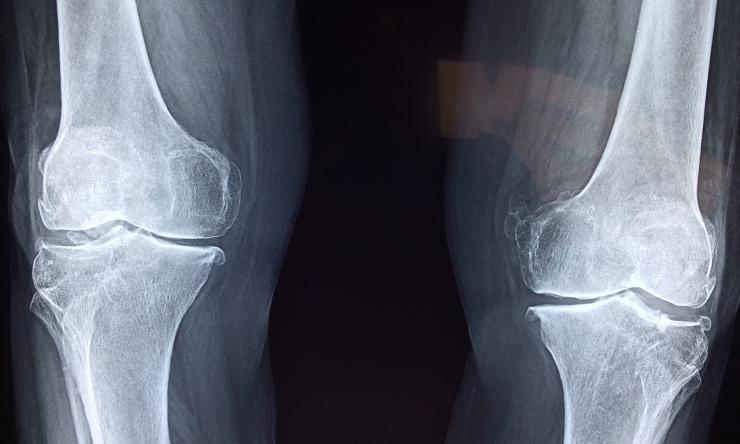

The mutation blocks the normal development of bone stem cells into mature cells, which would form healthy bones. Instead, the mutation leads to the formation of bones that are extremely brittle. Children with this disorder have recurrent fractures, bone deformities, chronic pain and other complications. The findings, published in The Journal of Clinical Investigation, offer new possibilities to design therapies for this yet untreatable condition.

The team discovered that the IFITM5 mutation acts at the level of bone stem cells, altering the normal process that leads to bone formation. “Bone stem cells lead the way in the formation of the skeleton during development and in bone healing after a fracture – first, they give rise to cartilage, which then turns into bone,” Lee said.

The Ifitm5 mutation in mice disrupts this process. Instead of progressing from cartilage to bone, progenitor cells form overgrown cartilage calluses where new bone should be.

“Our findings help explain what we see in patients with OI type V. They not only have bones that break easily, but when stem cells attempt to heal them, they form large calluses of cartilage instead of bone,” Lee said. “It’s like the stem cells do not finish the job, they get caught in a loop to preferably form cartilage, instead of maturing into bone.”